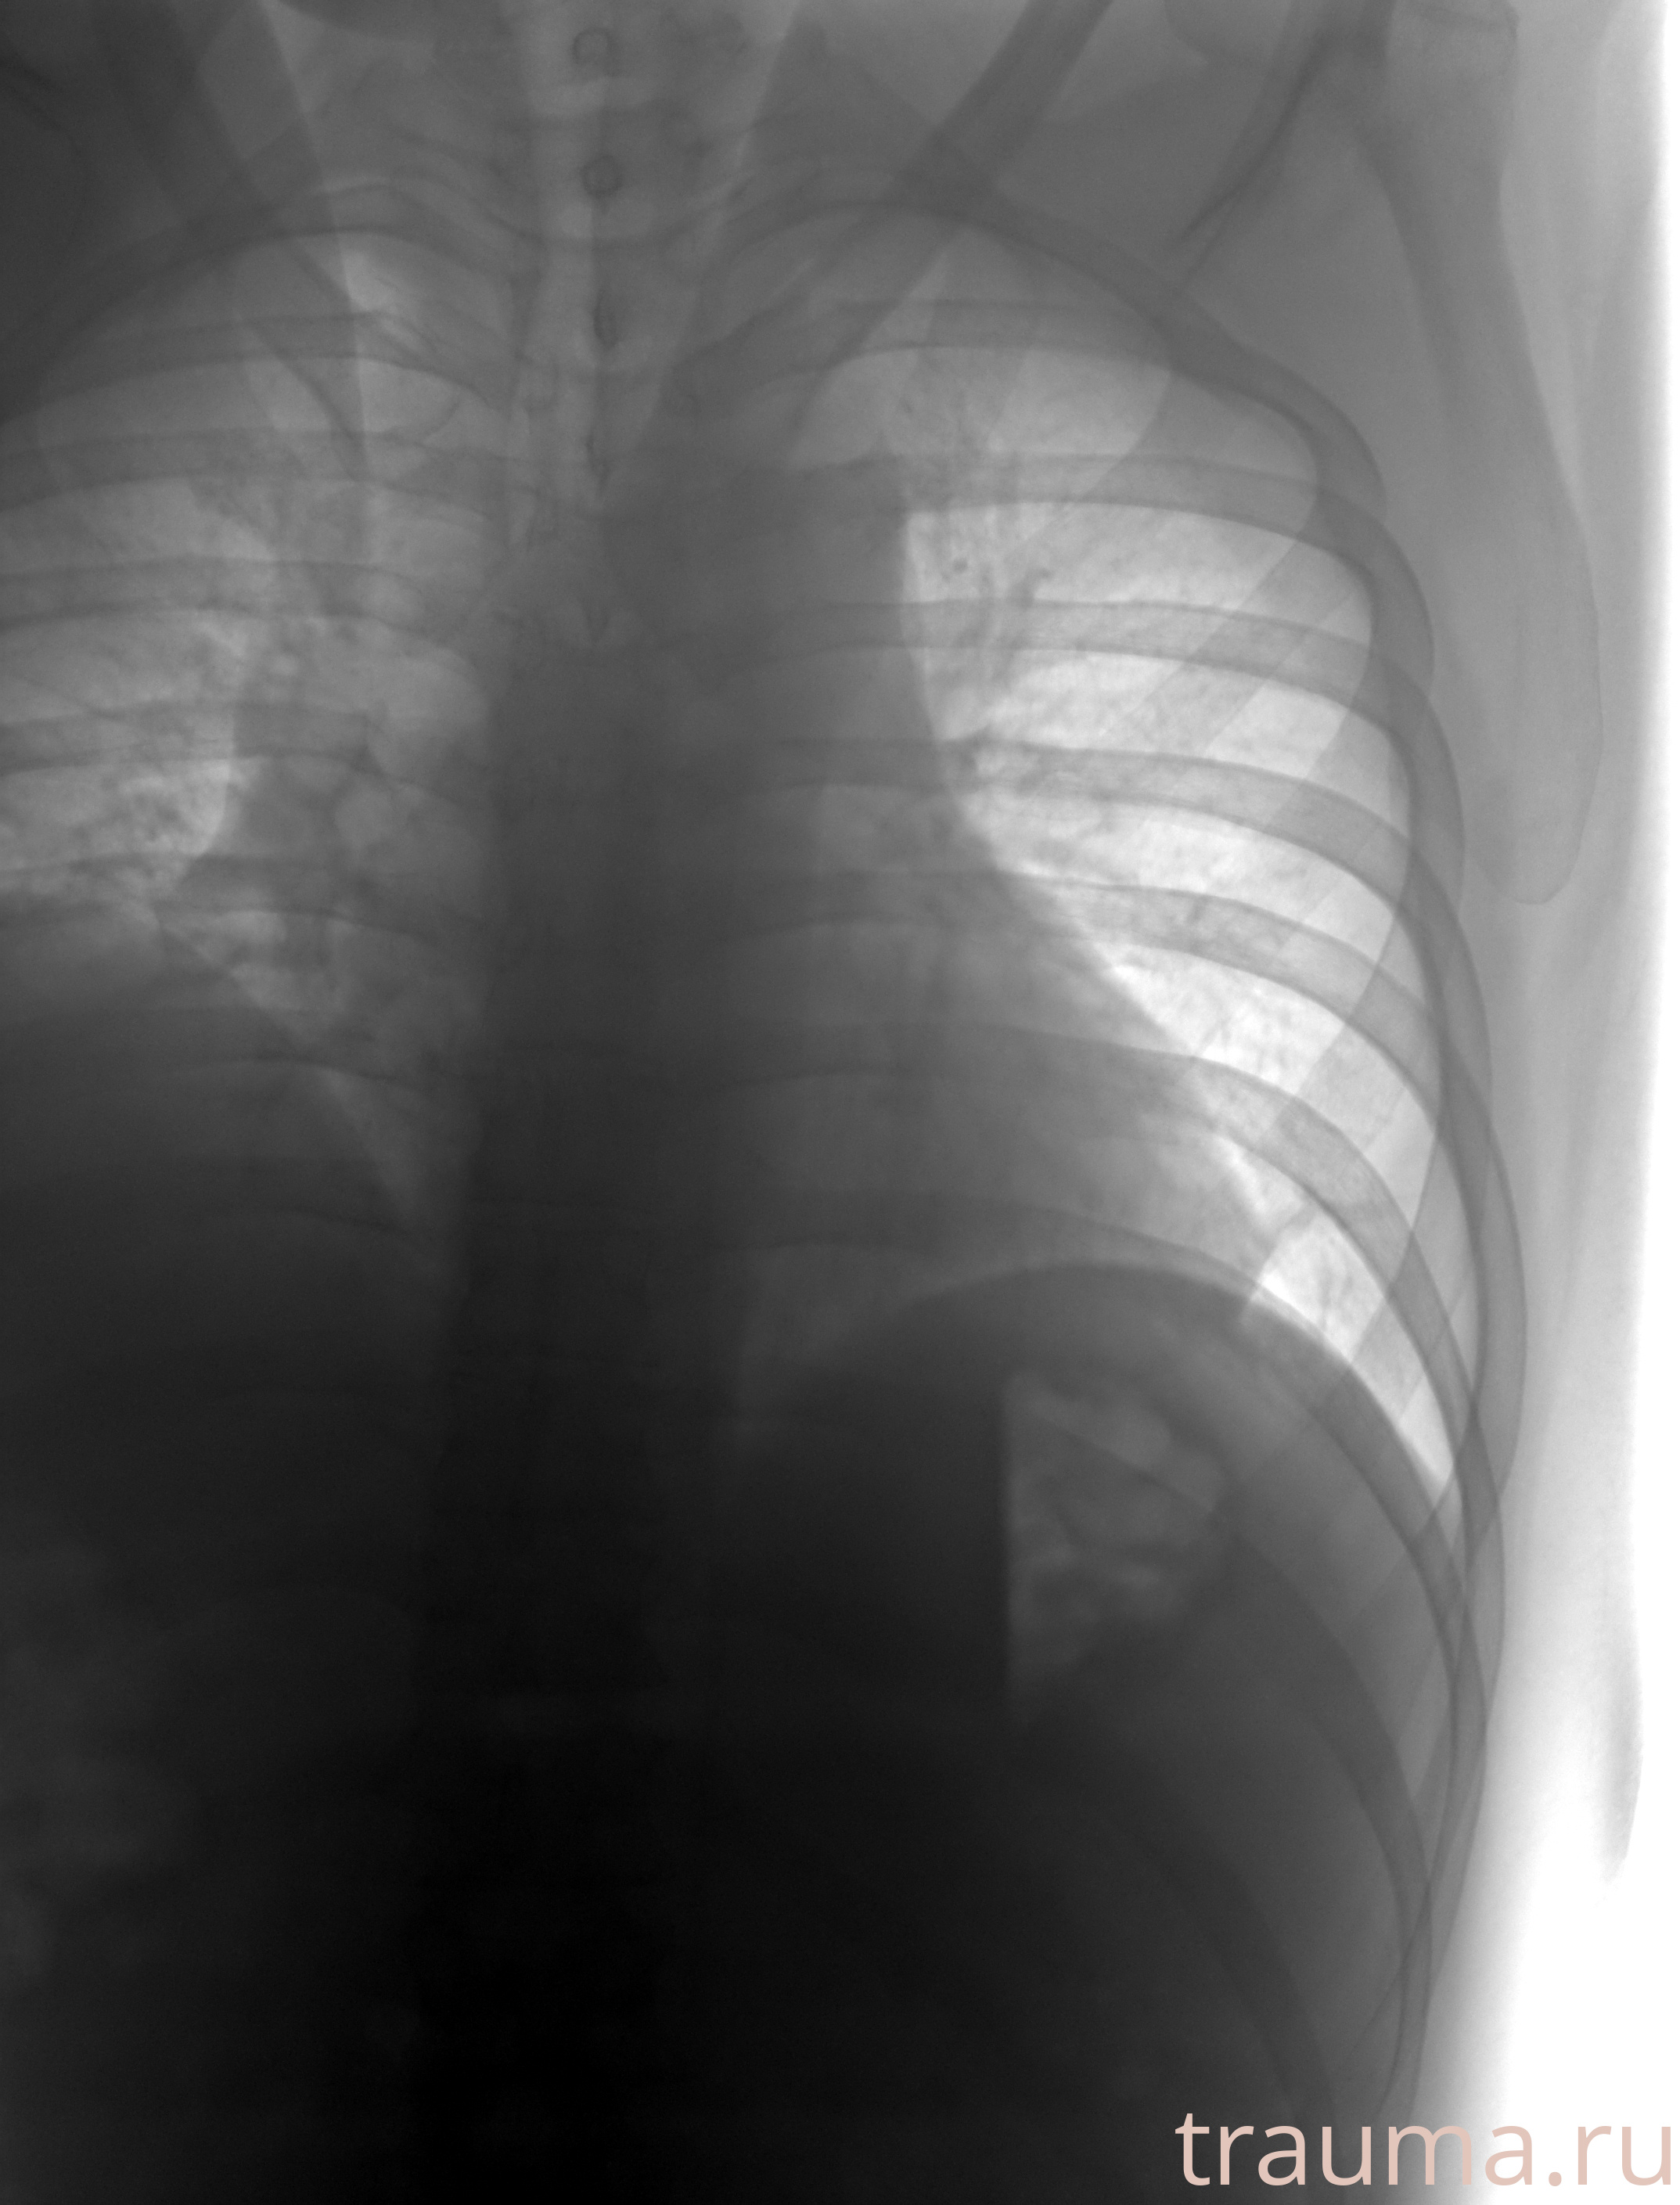

Рентгенограммы

Рентген на дому: по вашему адресу приезжает врач-рентгенолог, травматолог-ортопед с мобильным рентгеновским аппаратом, проводит диагностику травмы или заболевания, делает необходимые рентгенограммы, дает рекомендации по дальнейшему лечению. Получить качественные снимки в домашних условиях возможно благодаря уникальной методике, разработанной МосРентген Центром для института  Склифосовского